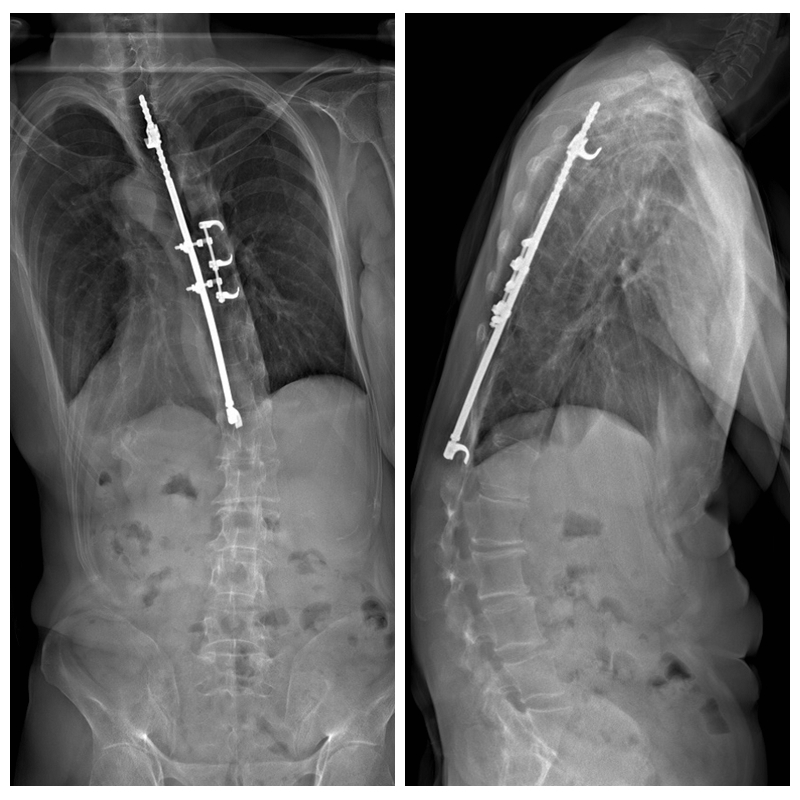

哈氏棒术后矢状位曲度失代偿(病例由Kawakami教授提供)